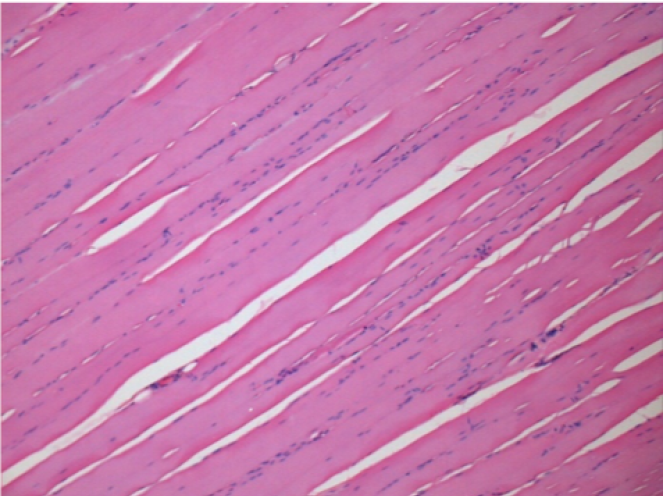

7 meses (D210) después de la inyección IM de Endopeel 0,1 ml en el músculo pretibial derecho.

Restitutio ad integrum (restauración a la condición original) completa después de 7 meses

L :Control 50xD210

R50X-D210